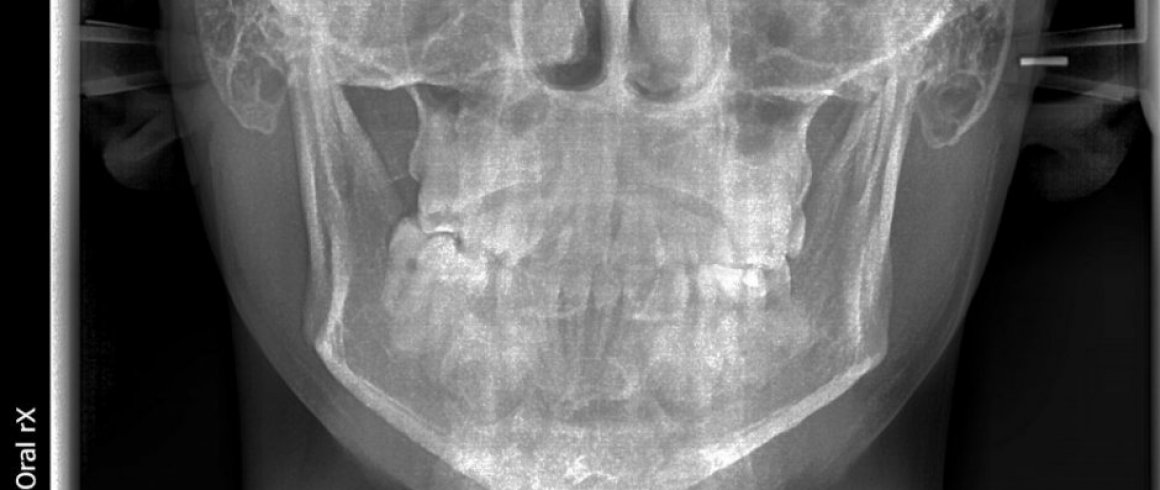

- Posteroanterior

- Radiografías Extraorales